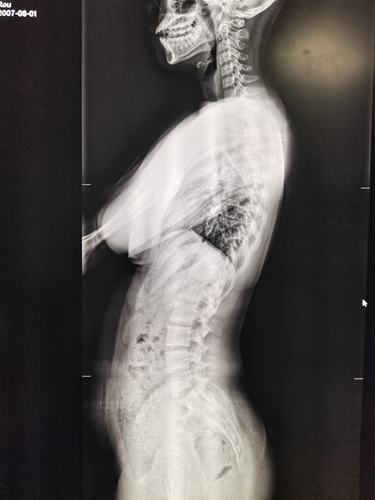

News近日,我院南区放射科首次通过数字影像处理技术获得满意的脊柱全长X光片,为脊柱畸形患者的诊断和治疗提供了重要的影像参考依据。

近年来,因为脊柱畸形问题来骨科就诊的人数增多,脊柱DR摄片只能分部位、分段式成像,医生想要获取患者脊柱全长影像资料,只能一张张读片,十分不便,且拼凑出的脊柱全长影像往往不够准确。而通过数字化图像处理后的脊柱全长正侧位片影像测量可获得相对准确的资料和数据,成为诊断脊柱侧弯最直接、最有效的手段,可以确定畸形的类型、部位,严重度和柔软性。摄片要求患者在站立位下摄脊柱全长正侧位片,以反映畸形的真实情况和躯干的平衡状态,对医生给予患者术前及术后评估提供了主要参考依据。

脊柱侧弯全长正位片 脊柱侧弯全长侧位片

近日,我院南区放射科工作人员在脊柱外科专家、我院朱泽章院长的指导下,通过DR成像系统及拼接软件进行脊柱全长成像技术,将获取的影像资料由图像后处理工作站经过窗宽、窗位调整及拼接软件的处理,形成一幅完整的全脊柱图像。该技术的应用,使人体颈椎、胸椎、腰椎、骶椎显示清楚,图像清晰,为医生的临床治疗工作提供了重要参考依据,还有利于资料保存,值得广泛推广。